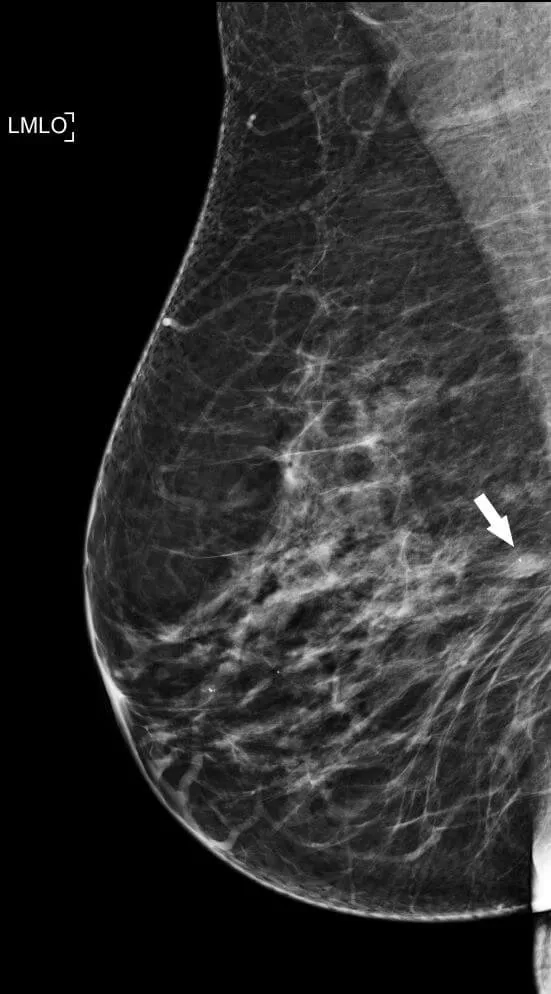

Left breast mammographic MLO view